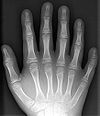

患有埃利偉氏綜合症的病人,可見他的兩手都是多指畸形及手指很短軟骨外胚層發育不全綜合徵又稱Ellis-van Creveld先天畸形綜合徵、先天性軟骨鈣化障礙心臟病綜合徵、軟骨外胚層發育異常綜合徵等,為常染色體隱性遺傳性疾病,表現為短肢型侏儒,常有先天性心臟病和智力障礙等。本病徵為常染色體隱性遺傳,病因尚不清楚。初生嬰兒即出現侏儒狀態,如四肢長骨短而粗、遠端指(趾)特別小,並能出現多指(趾)、頭髮、牙齒髮育較差,全身長骨骨骺端鈣化不全,此外,本病徵特點為同時有先天性心臟病,常見房間隔缺損、卵圓孔殘留、二尖瓣狹窄等。精神發育遲滯。

這種疾病會造成包括下列在內的許多異常症狀:軸後多指症(post-axial polydactyly);先天性心臟病(congenital heart defects),通常是心房中隔缺損(atrial septal defect);產前牙齒萌發(pre-natal tooth eruption);指甲營養失調與發育不良; 短肢侏儒症(short-limbed dwarfism),成人身高約106厘米到153厘米;短肋(short rib);部份兔唇(partial hare-lip);腕關節骨骼的畸形,原因是鉤狀骨(hamate)與頭狀骨(capitate)的融合。

中央多指畸形的右手原本這個疾病將也稱為“六指侏儒症”(Six-fingered dwarfism),這樣的名稱讓非專業人士較能簡單的了解這種罕見疾病。但後來這樣的名稱卻冒犯了某些族群,不是因為“侏儒”二字,而是因為“六指”被貼上了“怪異”的標籤。之後這個疾病最常用的名稱變成了“埃利偉氏綜合症”(Ellis-van Creveld syndrome)與縮寫EVC。另外兩個名稱,“軟骨外胚層發育不良症”(Chondroectodermal dysplasia)與“中外胚層發育不良症”(mesoectodermal dysplasia),則較為少用。